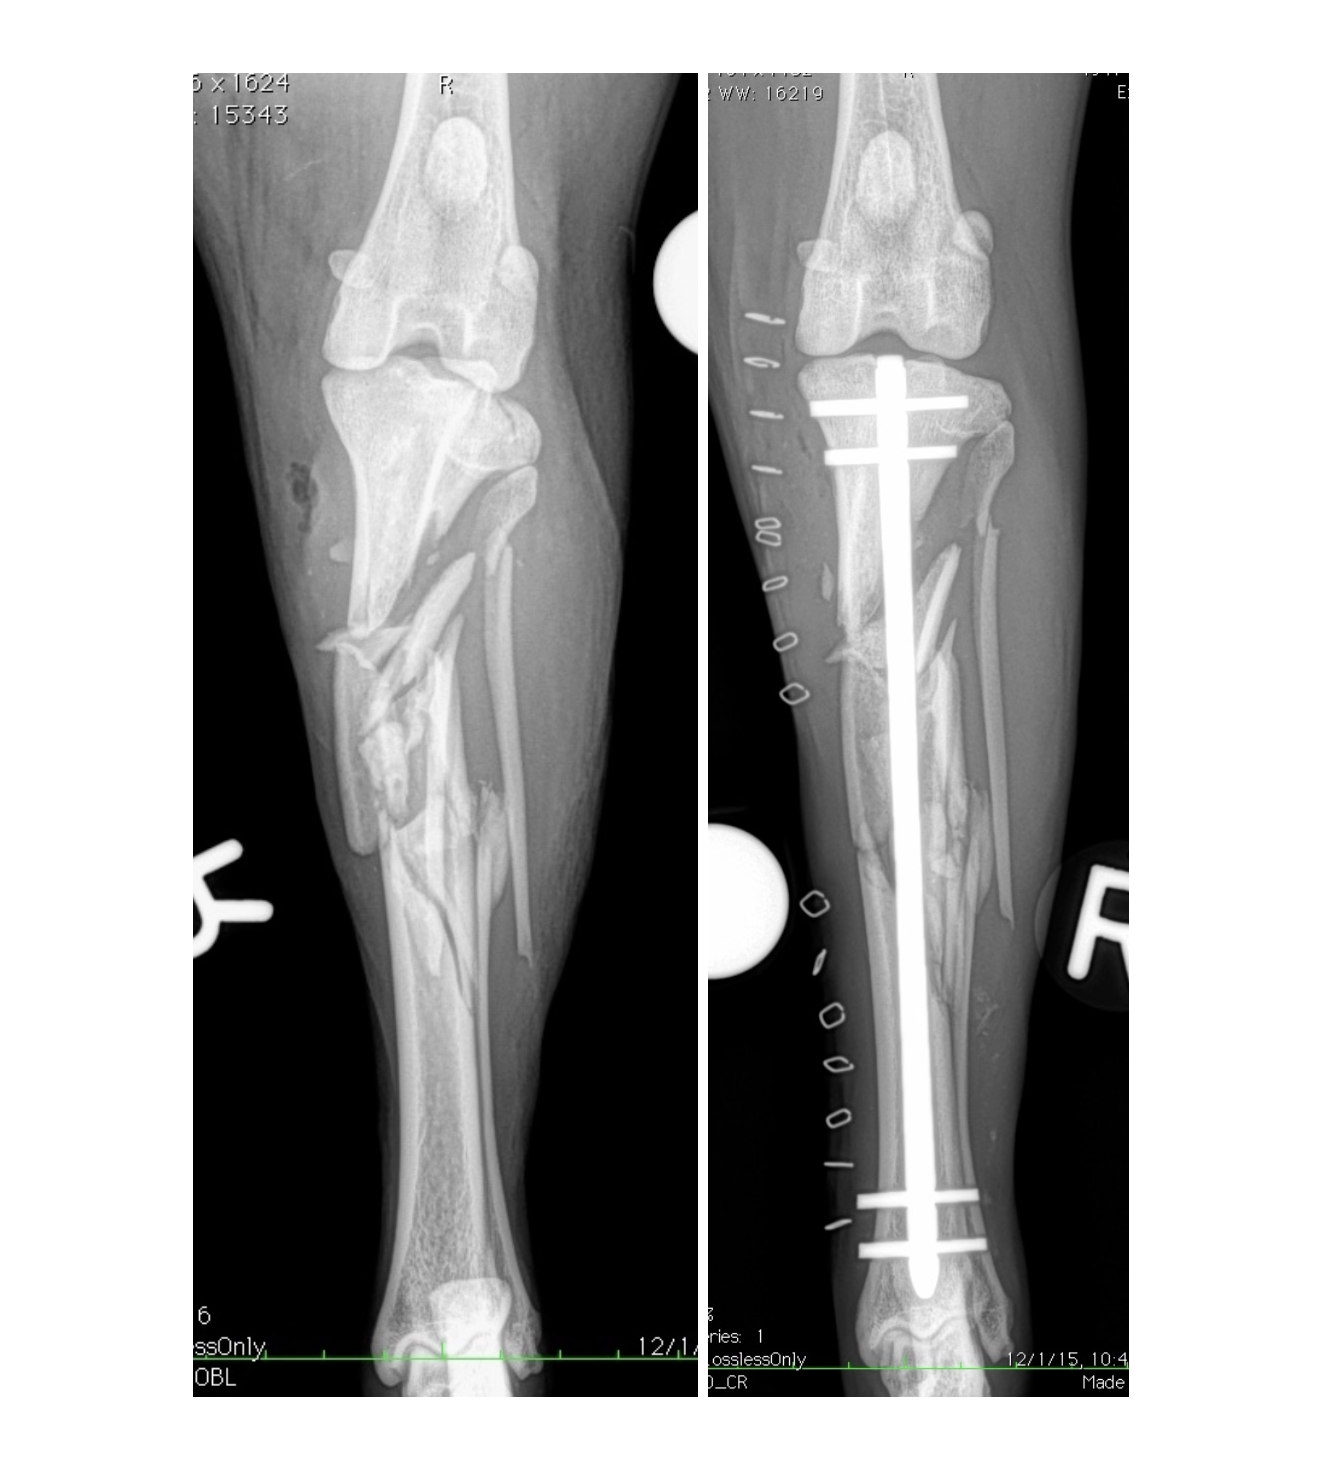

This highly comminuted tibia-fibula fracture in a Border Collie was managed with a Biomedtrix I-Loc interlocking nail (ILN). Many ILN applications in the tibia of dog's may be managed without opening of the fracture site and disruption to the fracture hematoma and local blood supply. These minimally-invasive techniques may help bones heal faster and with less complications.